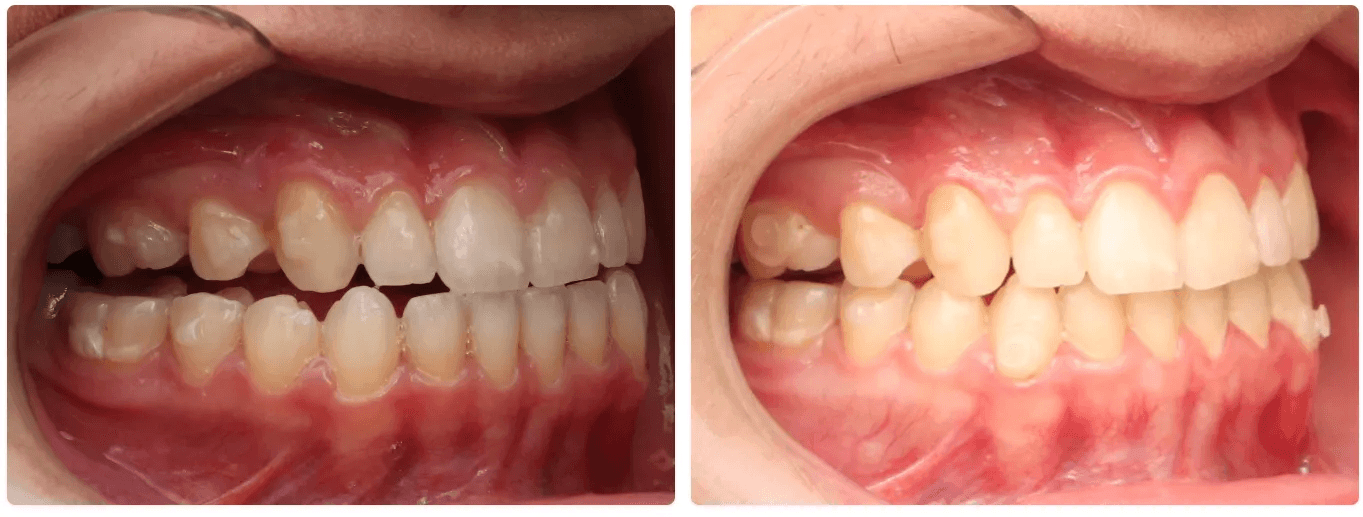

Correções de classe:

A correção de classe com alinhadores pode ser feita através de uma distalização sequencial ou por mesialização sequencial (Você pode conhecer um pouco sobre essas movimentações em Padrões de movimentação com os alinhadores) . Sempre é necessário mecânicas elásticas para tratamentos que envolvem correções de classe.

O uso do elástico pode acontecer com botões colados no dente ou com elásticos diretos no alinhador, depende da características de movimentação do canino principalmente

Tratamentos que envolvem correção de classe são tratamentos longos e que exigem cooperação do paciente pelo uso dos elásticos, o que deve ser conversado antes do início do tratamento. Casos de correção de meio dente ou mais ( no sentido anteroposterior) são indicações para Plano ez24

O alinhador pode fazer compensação de Classe II e Classe III esquelética, mas não substitui ortopedia ou cirurgia.